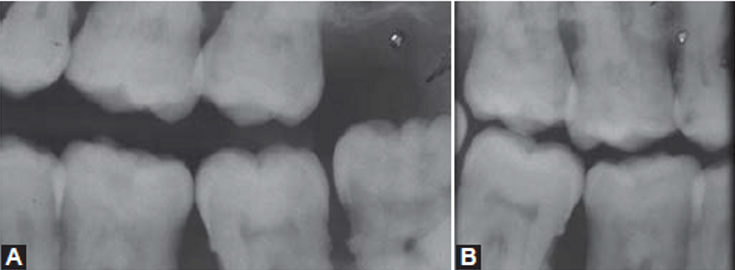

Las radiografías juegan un papel importante en el diagnóstico de la enfermedad periodontal, sin embargo, estas pueden tener limitaciones como en el caso de una la periodontal severa donde no se llegan a observar signos radiográficos de esta. Las proyecciones radiográficas útiles para el diagnóstico en periodoncia incluyen la radiografía periapical, la radiografía de aleta de mordida y la radiografía panorámica; siendo la radiografía periapical con técnica paralela la de principal elección para la evaluación de enfermedad periodontal, ya que la técnica de la bisectriz puede mostrar mayor o menor reabsorción ósea de la cual realmente presenta el paciente. Las radiografías de aleta de mordida tomadas verticalmente pueden utilizarse para evaluar la altura de la cresta ósea, cuando la perdida de esta ha sido considerable, siendo de mayor utilidad para la evaluación postratamiento o como una radiografía de seguimiento. Las radiografías de aleta de mordida tomadas horizontalmente no son útiles para evaluar la reabsorción óseas severas, pero son útiles para la evaluación de caries interproximal o recidivante. Entre las radiografías útiles para la evaluación periodontal, la radiografía panorámica es la de menor precisión ya que solo es útil para una evaluación general del soporte óseo alveolar. No obstante, esta radiografía tiene un campo amplio de evaluación para poder evaluar casos como terceros molares impactados bilaterales comprometiendo el hueso alveolar de una segunda molar o múltiples coronas protésicas desadaptadas y sobreobturaciones que condicionen la pérdida ósea alveolar, aunque en la mayoría de estos casos siempre será necesaria la ampliación del estudio con radiografías periapicales para una mejor evaluación de la zona.

Entre los factores predisponentes de enfermedad periodontal observables radiográficamente, se pueden observar irritantes locales como los cálculos o las restauraciones defectuosas. Los cálculos dentales corresponden a placa bacteriana acumulada y calcificada, las cuales se pueden observar como espículas irregulares radiopacas a nivel cervical por mesial o por distal; o pueden ser observadas también rodeando un diente en su zona cervical como un anillo radiopaco, sin embargo, pequeños depósitos de cálculos pueden pasar desapercibidos en una radiografía.